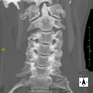

- TC Columna cervical

Prova radiològica que consisteix en obtenir imatges de les vèrtebres cervicals d'alta definició anatòmica, mitjançant l'ús d'un equip de TC (Tomografia Computeritzada). Indicacions: dolor cervical amb/sense irradiació als braços, traumatisme, malformacions congènites. - TC Columna dorsal

Prueba radiológica que consiste en obtener imágenes de las vertebras cervicales de alta definición anatómica mediante el empleo de un equipo de TC (Tomografía Computarizada). Indicaciones: cervicalgia sin/con irradiación a brazos, traumatismo.